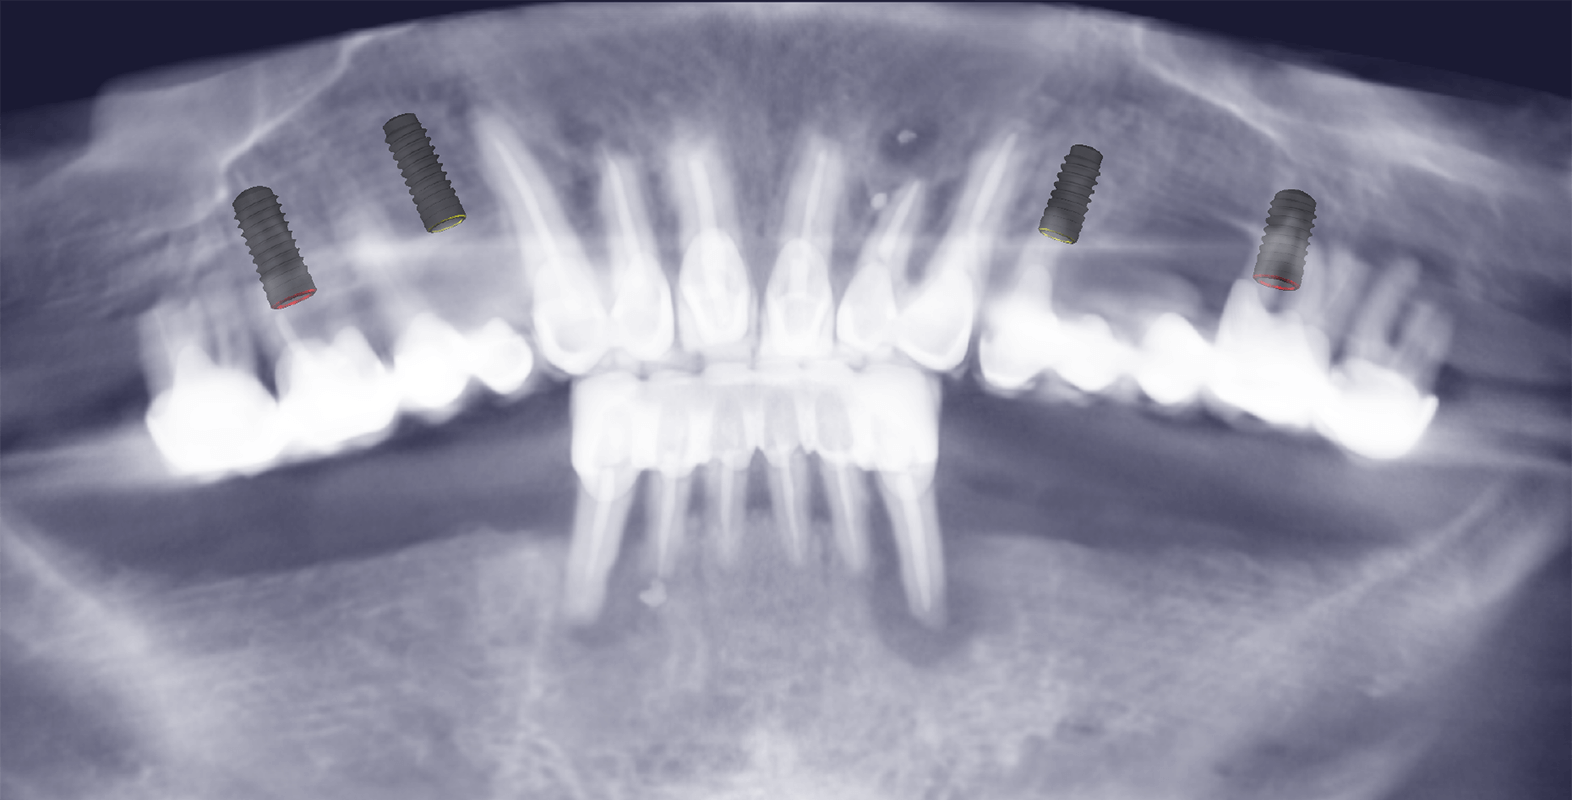

Через неделю пациента снова пригласили в клинику на контрольный осмотр. Дополнительно врач провел рентгенологическое исследование, на котором проследил как "села" конструкция и как спозиционировались абатменты в имплантах после нагрузки. Коррекция работы не потребовалась. После этого врач дал рекомендации по уходу, чтобы новые зубы прослужили пациенту как можно дольше: рекомендовалась профессиональная гигиена полости рта дважды в год, использование ирригатора в домашних условиях, контрольный рентген ежегодно.

В общей сложности лечение длилось 2 месяца и состояло из 7 посещений клиники. Пациенту установили 10 зубных имплантатов Straumann BLT и 24 ортопедические единицы из диоксида циркония в цвете Bleach 2.